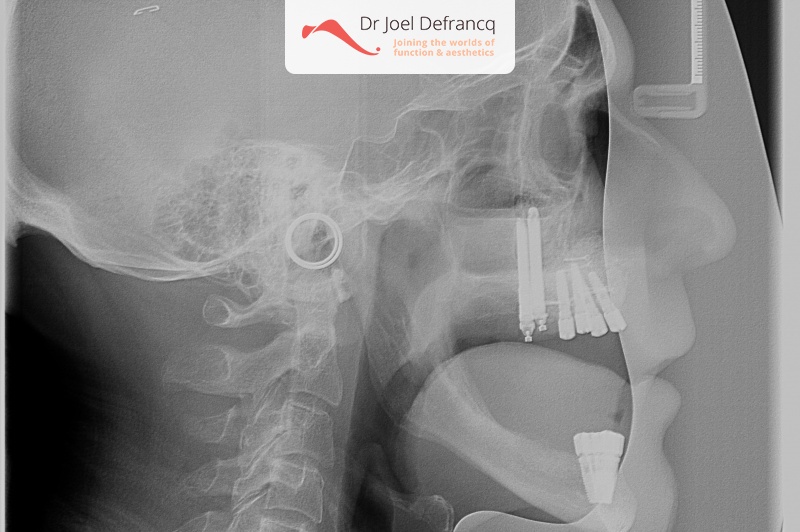

Dentale diagnose

- Klasse I

- Tandeloos